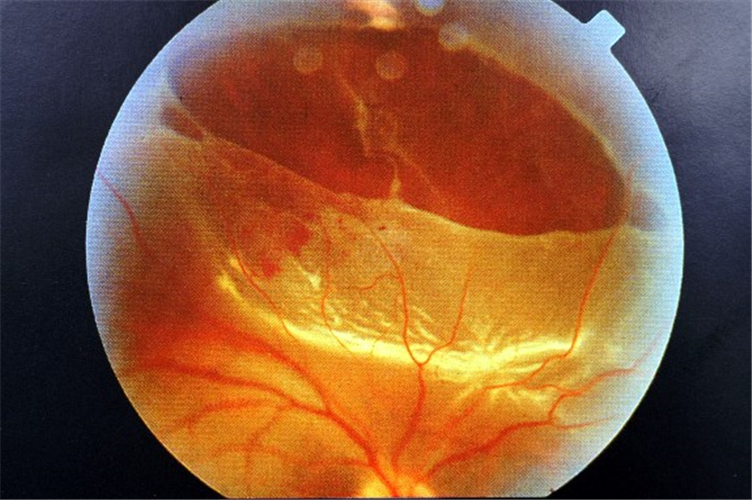

早產兒視網膜脫落

早產兒牽拉性視網膜脫落